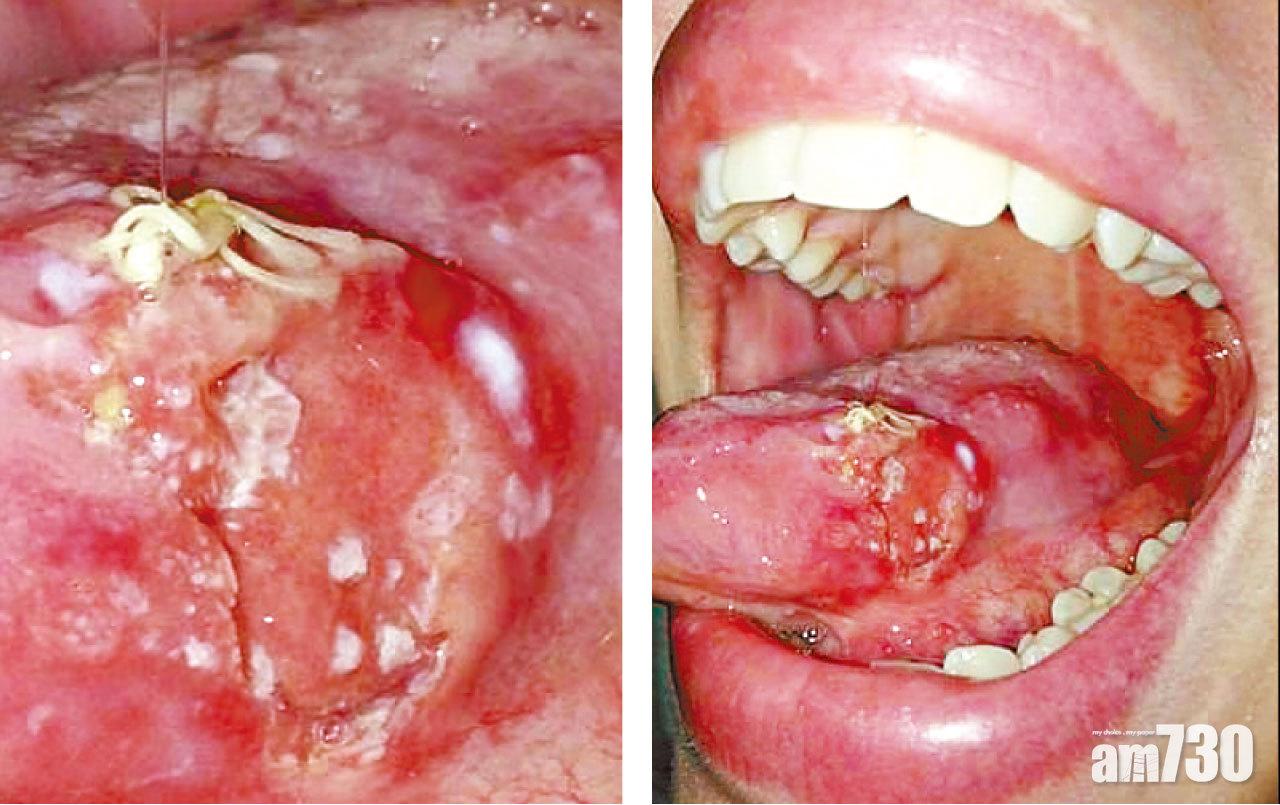

(左)癌細胞在口腔內擴散。右)癌細胞覆蓋舌頭。(互聯網)